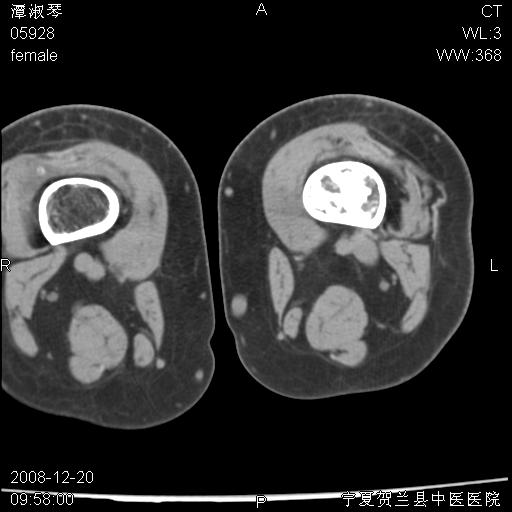

标题: CT17526:请各位看看是啥?

内生软骨瘤?骨梗死?

考虑内生软骨瘤可能性大

考虑-----骨梗死+退变

支持骨梗死,退行性骨关节病,膝关节积液.

考虑骨梗死可能性大

骨梗死可能性大

左股骨下段骨梗死。双膝退变。

左胫骨下端松质骨及髓腔内可见点片状高密度灶,骨皮质无明显膨胀及变薄。病变范围较长。支持骨梗死,退行性骨关节病,膝关节积液